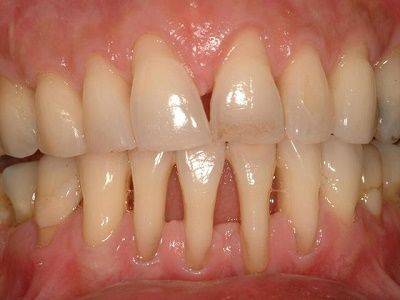

Атрофическое воспаление десен

Оголение передней группы зубов